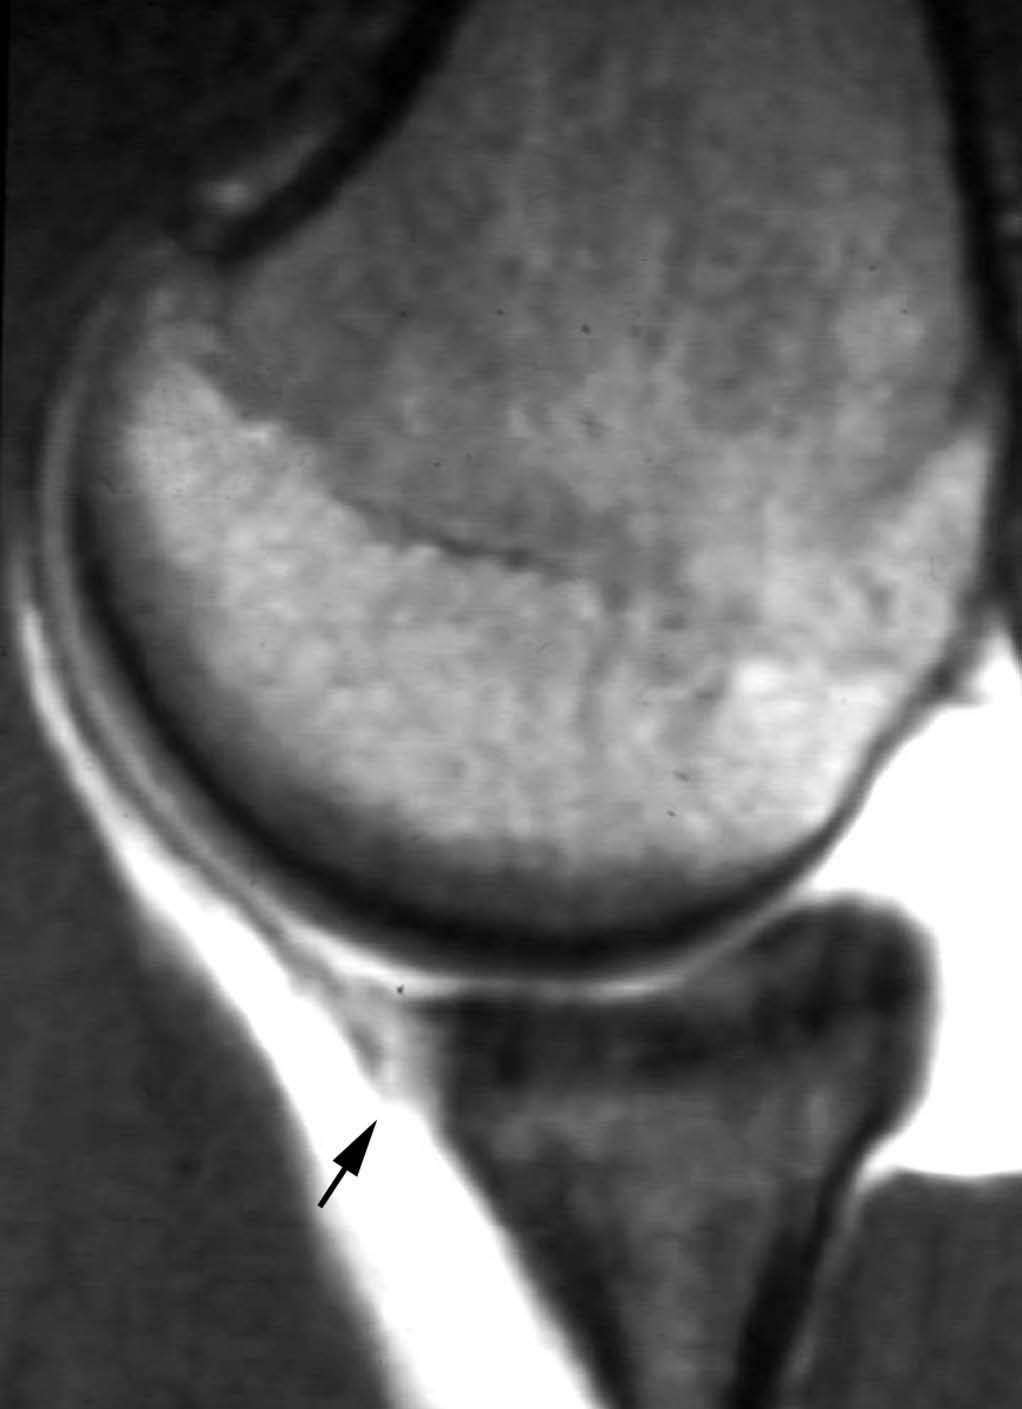

Lesión de Perthes

La lesión de Perthes es similar a la de Bankart, con la excepción de que no existe rotura capsuloperióstica, aunque el periostio puede estar separado del borde anterior del margen glenoideo (fig. 10). Esta lesión puede ser difícil de visualizar, incluso con artrorresonancia, a menos que se obtengan imágenes con la posición de abducción y rotación externa (ABER). En un estudio de 10 casos, verificados quirúrgicamente, Wisher et al17 comprobaron que el 50% de las lesiones de Perthes sólo podían visualizarse en la posición de ABER.

Fig. 10.--Lesión de Perthes. Artrorresonancia T1 con saturación grasa en posición ABER (abducción y rotación externa), donde se observa un arrancamiento parcial del labio glenoideo (flecha) con conservación de la unión capsuloperióstica.